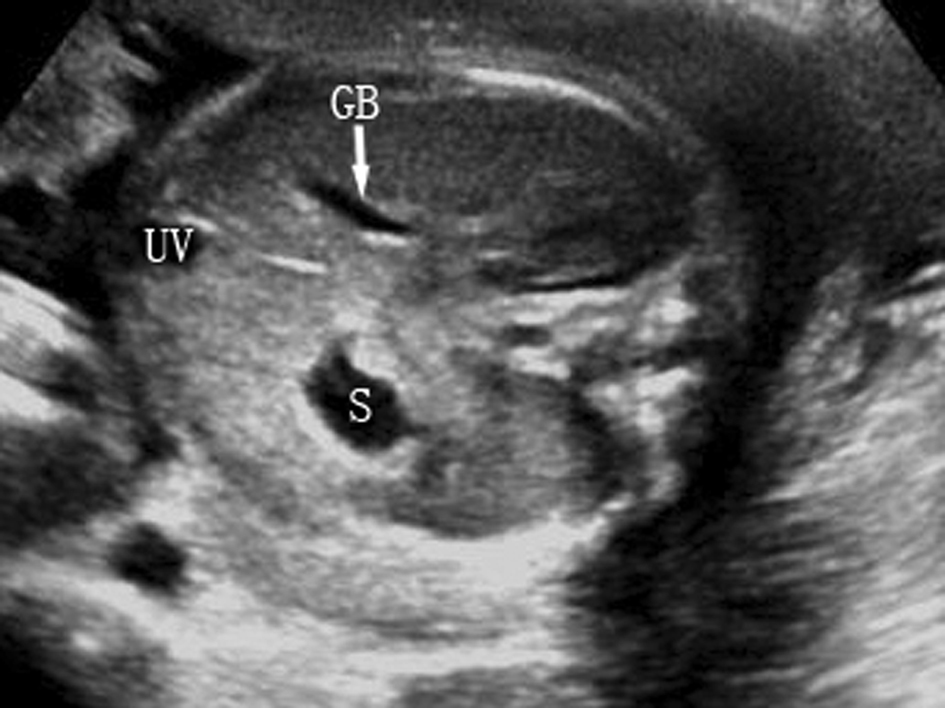

2.胆囊 14~16孕周后胎儿可显示胎儿胆囊回声(图2,GB)。正常胆囊长轴呈梨形,横切面呈类圆形,位于上腹部脐静脉(UV)腹腔段右侧,与脐静脉成一锐角,近腹壁但与腹壁不相连,无搏动,囊壁回声较脐静脉的管壁回声强,也较厚。当难以分辨胆囊与脐静脉时,可应用彩色多普勒超声进行鉴别。产前超声检查有时可显示胆囊结石、胆囊增大、胆囊水肿等,有报告染色体异常可能合并胆囊回声异常。

图2胎儿胆囊横切面声像图